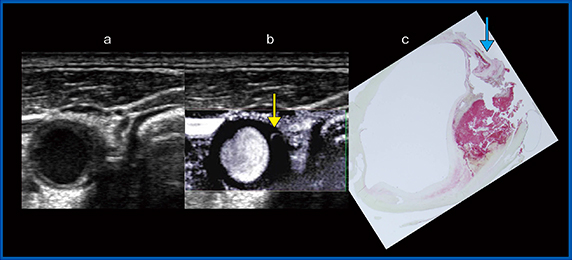

症例2は,74歳,男性,症候性プラークの症例である。Bモード(図4a)では,等輝度主体,一部高輝度な全周性プラークを認めた。SMI(図4b)では,↓に血流が描出された。この部分の狭窄は軽度だったが,血管のほかの部分に高度な狭窄があり,症候性でもあったことから頸動脈内膜剥離術(CEA)が施行された。手術で採取された検体の病理標本(図4c)では,超音波での所見と同様に全周性にプラークがあり,SMIで血流が描出されたのと同じ部位に新生血管(↓)が認められた。

図4 症例2:症候性の頸動脈プラーク

a:Bモード画像,b:SMI画像,c:病理画像(GPA染色)